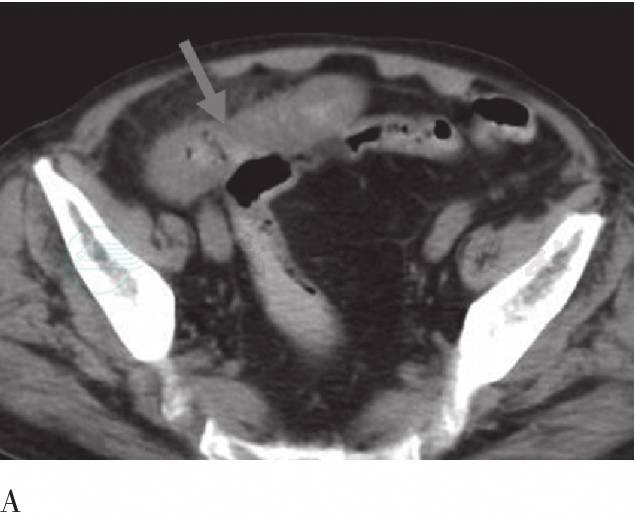

图3 FDG PET/CT腹部横断层图像

A、B分别为同层面CT、PET横断层图像;C、D分别为同层面CT、PET横断层图像;E、F为腹部连续CT横断层。远端回肠走形僵硬,肠壁弥漫性明显增厚,肠腔狭窄,范围较大,病灶周围脂肪间隙模糊、肠系膜增厚,PET于增厚的肠壁处见异常浓聚影,SUVmax为7.9,SUVave为4.0。肠系膜间可见到细小淋巴结,放射性分布未见增高